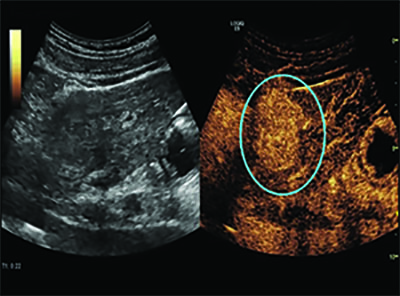

Therapeutic Approaches with Microbubbles

Dr. Forsberg’s colleague, John Eisenbrey, PhD, is in the early phase of a clinical trial studying UTMD on liver cancer patients undergoing radioembolization. The researchers introduced the microbubbles into the tumors and then destroyed them with acoustic waves, making the tumors more sensitive to the radiation. Follow-up imaging showed that of the seven patients who underwent UTMD, two experienced complete response to treatment and four had partial response. In contrast, only one of the four patients who did not undergo UTMD had a partial response and three had no response at all.

“We are about a quarter of the way into our ongoing clinical trial, but we think these preliminary efficacy results show us that there is potential for this to work,” Dr. Forsberg said.